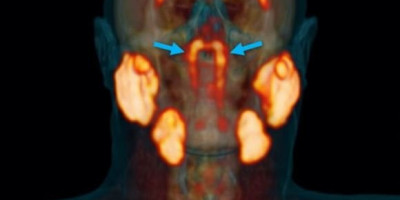

Otkrili su ih doktori u Holandiji dok su naprednim tipom skenera pregledali pacijente sa rakom prostate. Pacijentima su ubrizgali radioaktivnu glukozu da bi otkrili tumore u telu.

Međutim, otkrili su nešto neočekivano. U zadnjem delu nosnog dela ždrela (nazofarinksu) – iza nosa i iznad nepca, blizu centra glave – ugledali su velike pljuvačne žlezde.

„Ljudi imaju tri velike pljuvačne žlezde, ali ne ovde. Jedine pljuvačne i mukozne žlezde u nazofarinksu za koje smo znali su mikroskopski male i ima ih oko hiljadu ravnomerno raspoređenih. Možete da zamislite naše iznenađenje kada smo otkrili ove“, kaže radiolog Vojter Vogel sa holandskog Instituta za rak.

Pljuvačne žlezde luče pljuvačku, ključnu za funkcionisanje digestivnog sistema, a najveći deo proizvode tri velike žlezde – podjezična, podvilična i doušna (parotidna).

U glavi postoji još oko 1.000 manjih žlezda, ravnomerno raspoređenih oko usne šupljine, ali su one toliko male da bi mogle da se spaze bez mikroskopa.

Novo otkriće Vogelovog tima je mnogo veće, a čine dve prethodno neotkrivene žlezde, koje bi potencijalno mogle da postanu četvrta velika pljuvačna žlezda.